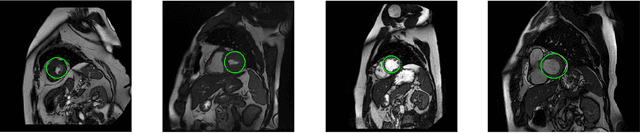

Abstract:Segmentation of the left ventricle in cardiac magnetic resonance imaging MRI scans enables cardiologists to calculate the volume of the left ventricle and subsequently its ejection fraction. The ejection fraction is a measurement that expresses the percentage of blood leaving the heart with each contraction. Cardiologists often use ejection fraction to determine one's cardiac function. We propose multiscale template matching technique for detection and an elliptical active disc for automated segmentation of the left ventricle in MR images. The elliptical active disc optimizes the local energy function with respect to its five free parameters which define the disc. Gradient descent is used to minimize the energy function along with Green's theorem to optimize the computation expenses. We report validations on 320 scans containing 5,273 annotated slices which are publicly available through the Multi-Centre, Multi-Vendor, and Multi-Disease Cardiac Segmentation (M&Ms) Challenge. We achieved successful localization of the left ventricle in 89.63% of the cases and a Dice coefficient of 0.873 on diastole slices and 0.770 on systole slices. The proposed technique is based on traditional image processing techniques with a performance on par with the deep learning techniques.